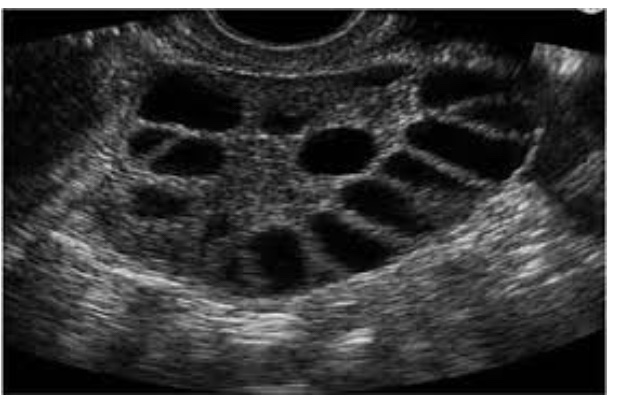

Polycystic Ovaries

Now that we can easily see very small cysts in the ovary on ultrasound we can use such studies to contribute to the diagnosis of PCOS. In spite of the name, having ovaries with multiple cysts does not necessarily mean that a woman has PCOS because they can be present in normal women and not all women with multicystic ovaries have PCOS. It is only when the cysts are accompanied by excess facial hair, thinning scalp hair and/or irregular menstrual cycles that the diagnosis is made.

The most common initial presentation of those with PCOS is irregular periods due to anovulation. Irregular cycles are very common in early adolescence so it is important to delay a diagnosis of PCOS until at least three years after the onset of menses unless the other two signs are present. In the normal menstrual cycle, only one follicle progresses from what is called a primordial follicle to a mature follicle which is released by the ovary (ovulation). In PCOS, multiple primordial follicles start the process but are unable to complete it due to an excess of the male hormone testosterone. These arrested follicles form tiny cysts that can be seen on USG. The failure of even a single egg to reach maturity in some or all cycles is the reason why so many women with PCOS may have difficulty becoming pregnant. Those enlarged ovaries have also been known to cause chronic pelvic pain.